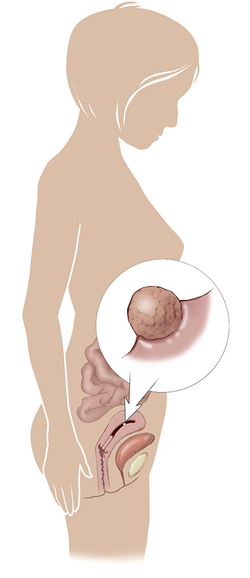

مراحل تطور الجنين أثناء الحمل

تطور الجنين خلال فترة الحمل على ثلاثة مراحل: أول 14 أسبوع من الحمل ، ثم تطوره بداية من الأسبوع 14 وحتى 28 أسبوعا ، ثم الثلث الأخير من 28 إلى 40 أسبوع من الحمل ... المزيد

مراحل تطور الحمل أسبوعيا بالصور

مراحل تطور الحمل أسبوعيا لكل من الأم والجنين داخل الرحم مدعومة بالصور التوضيحية ... المزيد